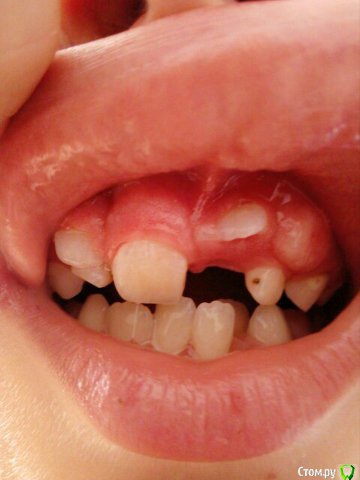

Opdihatop Опубликовано 9 января, 2017 Поделиться Опубликовано 9 января, 2017 Здравствуйте, коллеги! Хотел бы узнать ваше мнение по пациентке. Девочке 7 лет. План лечения в общем мне ясен и понятен. Меня интересует вопрос, когда лучше в данном случае убирать сверхкомплектный премоляр в области 21 зуба, потому что он начал двигать ц.л. вправо. Заранее спасибо! Ссылка на комментарий

Давлетшин Опубликовано 12 января, 2017 Поделиться Опубликовано 12 января, 2017 (изменено) С позиции детского амбулаторного хирурга-стоматолога я не трогал бы до окончания формирования корней, а 61, 62 убрал бы. Просто не лез, и не лезу. Да возможно есть есть очень хорошие хирурги с седацией и т.п. пусть они (он, она) решает. Из личного опыта у ребенка сверхкомплектный мешал прорезыванию 21 в семь лет, я все обьяснил сказал:" давайте ждать". Родители понимающе сказали:" давайте", и пошли снова к ортодонту, та в свою очередь отправила к своему "крутому" хирургу. Соответственно сверхкомплектный был удален (сверхкомлектный не прорезался) а у 21 сформирована была только коронка. Через три года, в 10 лет пришли снова, и у меня спрашивают:" где зуб"? Я направил на R-грамму, где увидел что коронка 21 "плавает" в очаге разряжения костной ткани размером 1.5*1.5 см. слизистая была в норме. Об"яснил, рассказал, показал риски для 11 и 22 зуба. и не сформированный 21 был удален. Причем после разреза слизистой и надкостницы с небной стороны сам выпал из полости "кисты". Не знаю где были ошибки. может мне надо было проявить эмоции и внушить что не надо удалять. Не знаю каков был ход операции, задели не задели ростковую зону 21 зуба, нарушили что нибудь не нарушили. Факт что ребенок остался без переднего зуба. Хорошо, мне хватило ума не лезть туда. Может ошибка родителей что не успокоились, и начали панику проявлять. Хирурга в той частной уже не было, наверно импланты крутит. Причем в разделе детская стоматология - есть мой фотоотчет по одонтоме. Т е если нет рисков повредить зачаток (зону роста корня)я лезу. Надо взвесить риски, сейчас что то делать, или же в 10-12 лет вытаскивать 21,22 зубы после формирования корней. Хорошо будет если срезы КТ добавите трансверсали. Даст Бог доучусь в орде на ортодонта, и начав работать ортодонтом думаю не изменю мнения при этом случае, зная работу детского хирурга. Снимков, КТ предоставить не могу потому, что шороха много было, оформления, переписывания карточки много было. Естественно когда я консультировал я все на словах говорил, через три года и не вспомнить. Ортодонт ни при чем, я типа не отправляла, они сами. Они кричали что именно ортодонт именно к определенному хирургу отправила, хирурга там уже давно и нет, и контора поменяла название. Кароч заведующая карточку под три замка в сейф свой убрала.Извините если много букв. Изменено 12 января, 2017 пользователем Давлетшин 1 Ссылка на комментарий

Yana guapa Опубликовано 13 января, 2017 Поделиться Опубликовано 13 января, 2017 убрать молочный ц. резец. подождать 6-8 месяцев хотя бы (лучше год) - все ростковые зоны уже значительно выше будут, хирург не задет уже.сделать КТ. и удалить сверхкомплектный. Дать возможность опуститься ц. резцу.сильно долго ждать (до полного формирования корней) не вижу смысла. Очень похожа ситуация была у моей девочки (такое же расположение). - очень долго не хотел ц. резец спускаться. Райц-терапия в помощь)) вышел)) Ссылка на комментарий

Yana guapa Опубликовано 19 января, 2017 Поделиться Опубликовано 19 января, 2017 Спасибо за снимки и рассказанный случай! конечно, и про такие истории надо знать! отправила к своему "крутому" хирургу. Соответственно сверхкомплектный был удален возможно он оказался не так крут! потому что многое действительно зависит от специалиста. Если элементарный зуб "самый крутой хирург в самой крутой клинике" удаляет ломая все стенки.... то что тут говорить про сверхкомплектный глубоко в кости, ростковые зоны и прочее... Поэтому все таки, я за удаление через 8 мес. у хорошего ответственного хирурга. Ссылка на комментарий